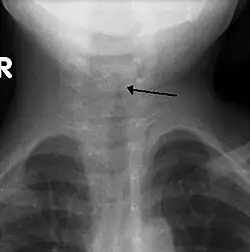

Kirchturm-Zeichen

Das Kirchturm-Zeichen (engl. steeple sign) ist ein radiologisches Zeichen, das eine subglottische Einengung der Luftröhre auf einer a.p.-Röntgenaufnahme zeigt. Es ist typisch für die subglottische Laryngotracheobronchitis (Pseudokrupp).[1]